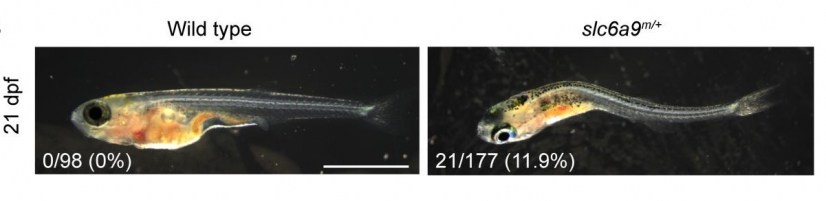

The team revealed that these identified variants in SLC6A9 resulted in reduced glycine uptake activity, leading to an increased glycine level and aberrant glycinergic neurotransmission. To further validate their findings, the team developed a novel zebrafish model with a disrupted SLC6A9 gene, mirroring the gene changes observed in humans with AIS. The mutant zebrafish exhibited spinal curvature and discoordination of spinal neural activity, resembling the symptoms found in AIS patients.